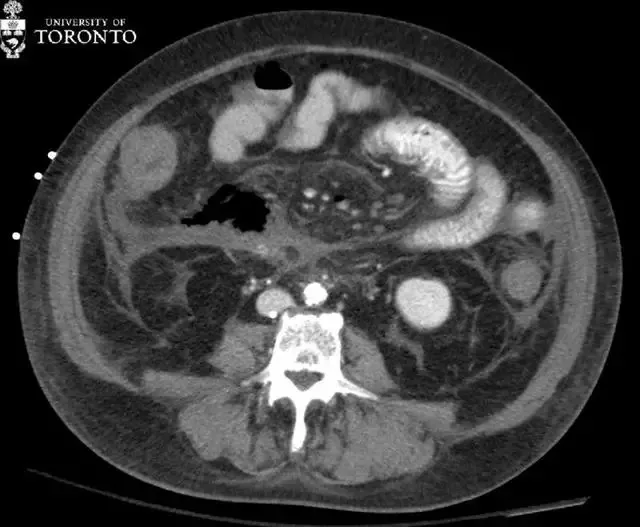

【治疗|精选病例:典型的急性坏死性胰腺炎】治疗:患者静脉用抗生素治疗了两个星期 , 之后患者出现了大量的混合性腹水 , 胰床上见 aeric 脓肿 , 位于钩突下方右侧可见另一个腹膜后脓肿(黄色箭头) 。

两处脓肿分别在超声引导(右)和 CT 引导(左)下行经皮穿刺引流术 。 16-Fr 多功能引流导管放置在脓肿中 , 吸出带碎屑的脓液 。 在随访的 CT 引导下引流中 , 排水管处于较好的位置(粉红色箭头) , 脓肿的大小也减少 , 但不幸的是 , 病人在出现肠系膜缺血不久后死亡 。

胰腺脓肿可使坏死或非坏死性胰腺炎变的更复杂 , 通常在出现症状四周后才确诊 。 治疗方法是经皮或手术引流 。 在 CT 上 , 表现为包裹性积液 , 周围可见强化;内可能含有气泡(20%) 。 感染性假性囊肿需要与其相鉴别 , 它出现较晚 , 且往往与非感染假性囊肿具有相同的表现 。